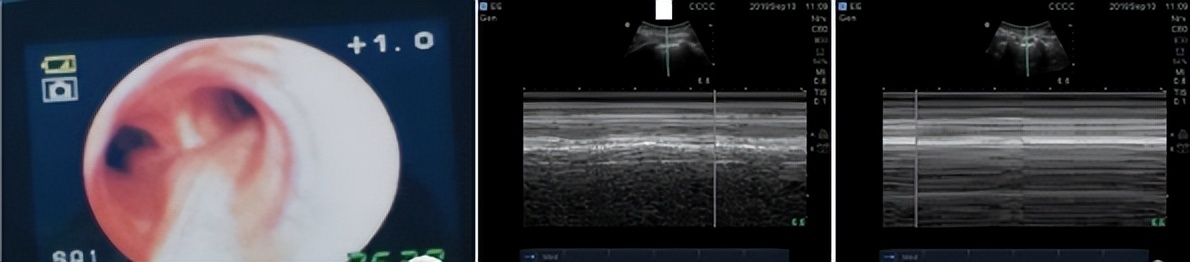

术中自发性气胸诊断:呼末CO 2 增高、气道压增高、颈静脉怒张、氧和降低、潮气量降低,胸、颈部可触及皮下气肿,听诊患侧呼吸音消失,叩诊可闻及鼓音。 辅助检查如X线:肺野内见外凸孤形的细线条形阴影,即为气胸线,线内为压缩的肺组织,线外为不含肺纹理强透光区。超声:B线消失、胸膜滑行征消失、肺搏动消失、 肺点 (“沙滩征”与“条码征”相互过渡的区域,在M型超声上,正常的胸膜滑动征表现为“沙滩征”,气胸时则变为“条码征”,但以“肺点征”对气胸的特异性最大,可达100%)。

考虑调整体位时气管插管可能进入右主支气管。但纤维支气管镜显示气管导管位置正常,没有分泌物阻塞右支气管。立即进行胸部超声检查。左肺:胸膜滑动和沙滩征标志,右肺:无胸膜滑动和条码征。